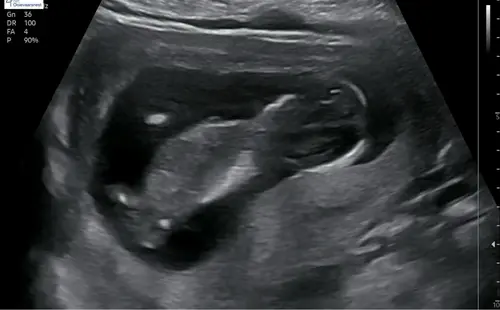

Ik vind het zo knap dat mensen hier wijs uit komen, ik kom er zelf maar niet uit, maar ben stiekem ook wel benieuwd of onze 2de een jongen of meisje is, kan iemand helpen? 😊

Alvast bedankt !

Wellicht dat ik hier tussen kom haha.. ziet iemand wat het is?😂

Duidelijk meisje!